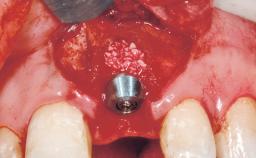

Immediate Flapless Placement of an Implant in a Maxillary Right Lateral Incisor Site

This 43-year-old male patient, a non-smoker, came to our practice because of a fracture of tooth 12 caused by a bicycle accident. Due to the combined para- and infrabony crown and root fracture, tooth extraction, and subsequent implant placement were suggested to the patient as the therapy of choice. The patient had high esthetic expectations with regard to the treatment outcome and asked for an immediate fixed provisional restoration. His individual esthetic risk profile summed up to a medium esthetic risk.

| Placement Protocol | Immediate implant placement |

| Tooth Site | Maxillary incisor or canine |

| Socket Integrity | Sufficient, with intact bone walls |

| Bone Volume | Sufficient, with intact walls |

| Esthetic Risk | Medium |

| Risk of Complications | High |